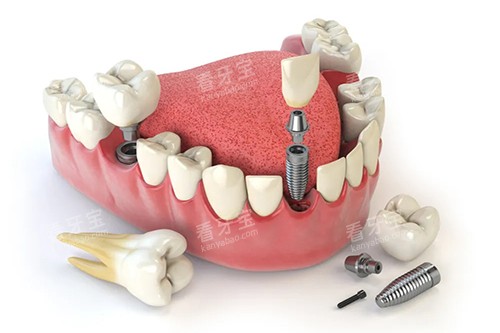

在牙齿种植方面,配备了智能化种植系统,该系统可以通过三维成像技术正确地分析患者口腔的骨骼结构、神经分布等情况,为种植方案的制定提供精密的数据支持,大大提高了种植手术的成功概率和靠谱性。

例如,在牙齿种植方面,医生们会根据患者的牙槽骨条件、身体状况等因素,选择合适的种植体和种植方法,确保种植结果达到较佳。

在牙齿种植方面,医院使用的种植体都是经过地区食品药品管控管理总局认证的合格产品,具有良好的生物相容性和稳定性。